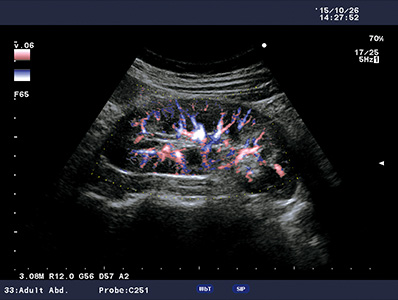

DFI is a new imaging technology for visualization of low velocity blood flow with greater resolution and sensitivity below the previous detection threshold.

Provides clearer delineation between tissue and blood flow compared to conventional Color Doppler. Even low velocity flow can be imaged with high sensitivity.

Real-time B- and Color Flow modes can be displayed side-by-side, offering an easier anatomical interpretation of blood flow.